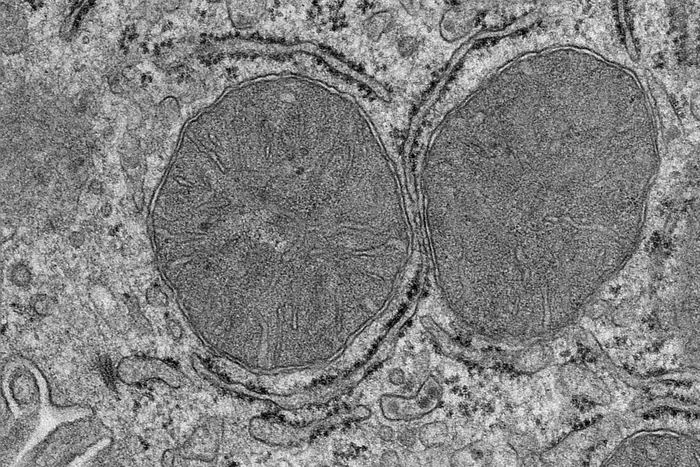

What happens in the body when we are hungry and see and smell food? A team of researchers at the Max Planck Institute for Metabolism Research has now been able to show in mice that adaptations in the liver mitochondria take place after only a few minutes. Stimulated by the activation of a group of nerve cells in the brain, the mitochondria of the liver cells change and prepare the liver for the adaptation of the sugar metabolism. The findings, published in the journal Science, could open up new avenues for the treatment of type 2 diabetes.

The researchers fed hungry mice that could only see and smell the food without eating it. After just a few minutes, the researchers analysed the mitochondria in the liver and found that processes normally stimulated by food intake were activated.

The studies show that it is sufficient for the mice to see and smell food for a few minutes to influence the mitochondria in the liver cells. This is mediated by a previously uncharacterised phosphorylation in a mitochondrial protein. Phosphorylation is an important modification for the regulation of protein activity. The researchers also show that this phosphorylation affects the sensitivity of the liver to insulin. The researchers have thus discovered a new signalling pathway that regulates insulin sensitivity in the body.

"When our senses detect food, our body prepares for food intake by producing saliva and digestive acid. We knew from previous studies that the liver also prepares for food intake. Now we have taken a closer look at the mitochondria in liver cells, because they are essential cell organelles for metabolism and energy production, and realised how surprisingly fast this adaptation takes place," explains Sinika Henschke, first author of the study.